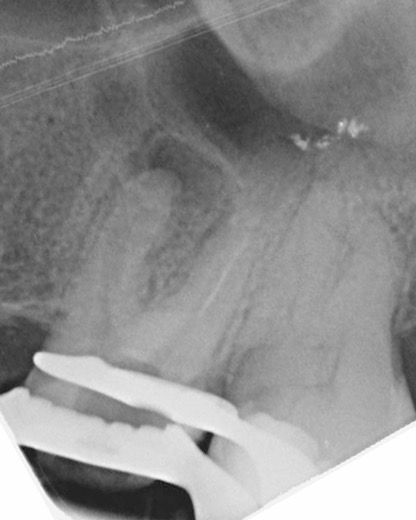

45 yaşında sağlıklı kadın hasta, 2023 Mayıs ayında protetik gereksinimden dolayı prepare edilen 26 numaralı dişinde işlem sonrası gelişen şiddetli ağrı şikayeti ile kliniğimize başvurdu İlgili dişe kök kanal tedavisi işlemi planlandı (Şekil 1).

(Şekil 1) 2023 Mayıs 26 No Pre-Op radyografi.